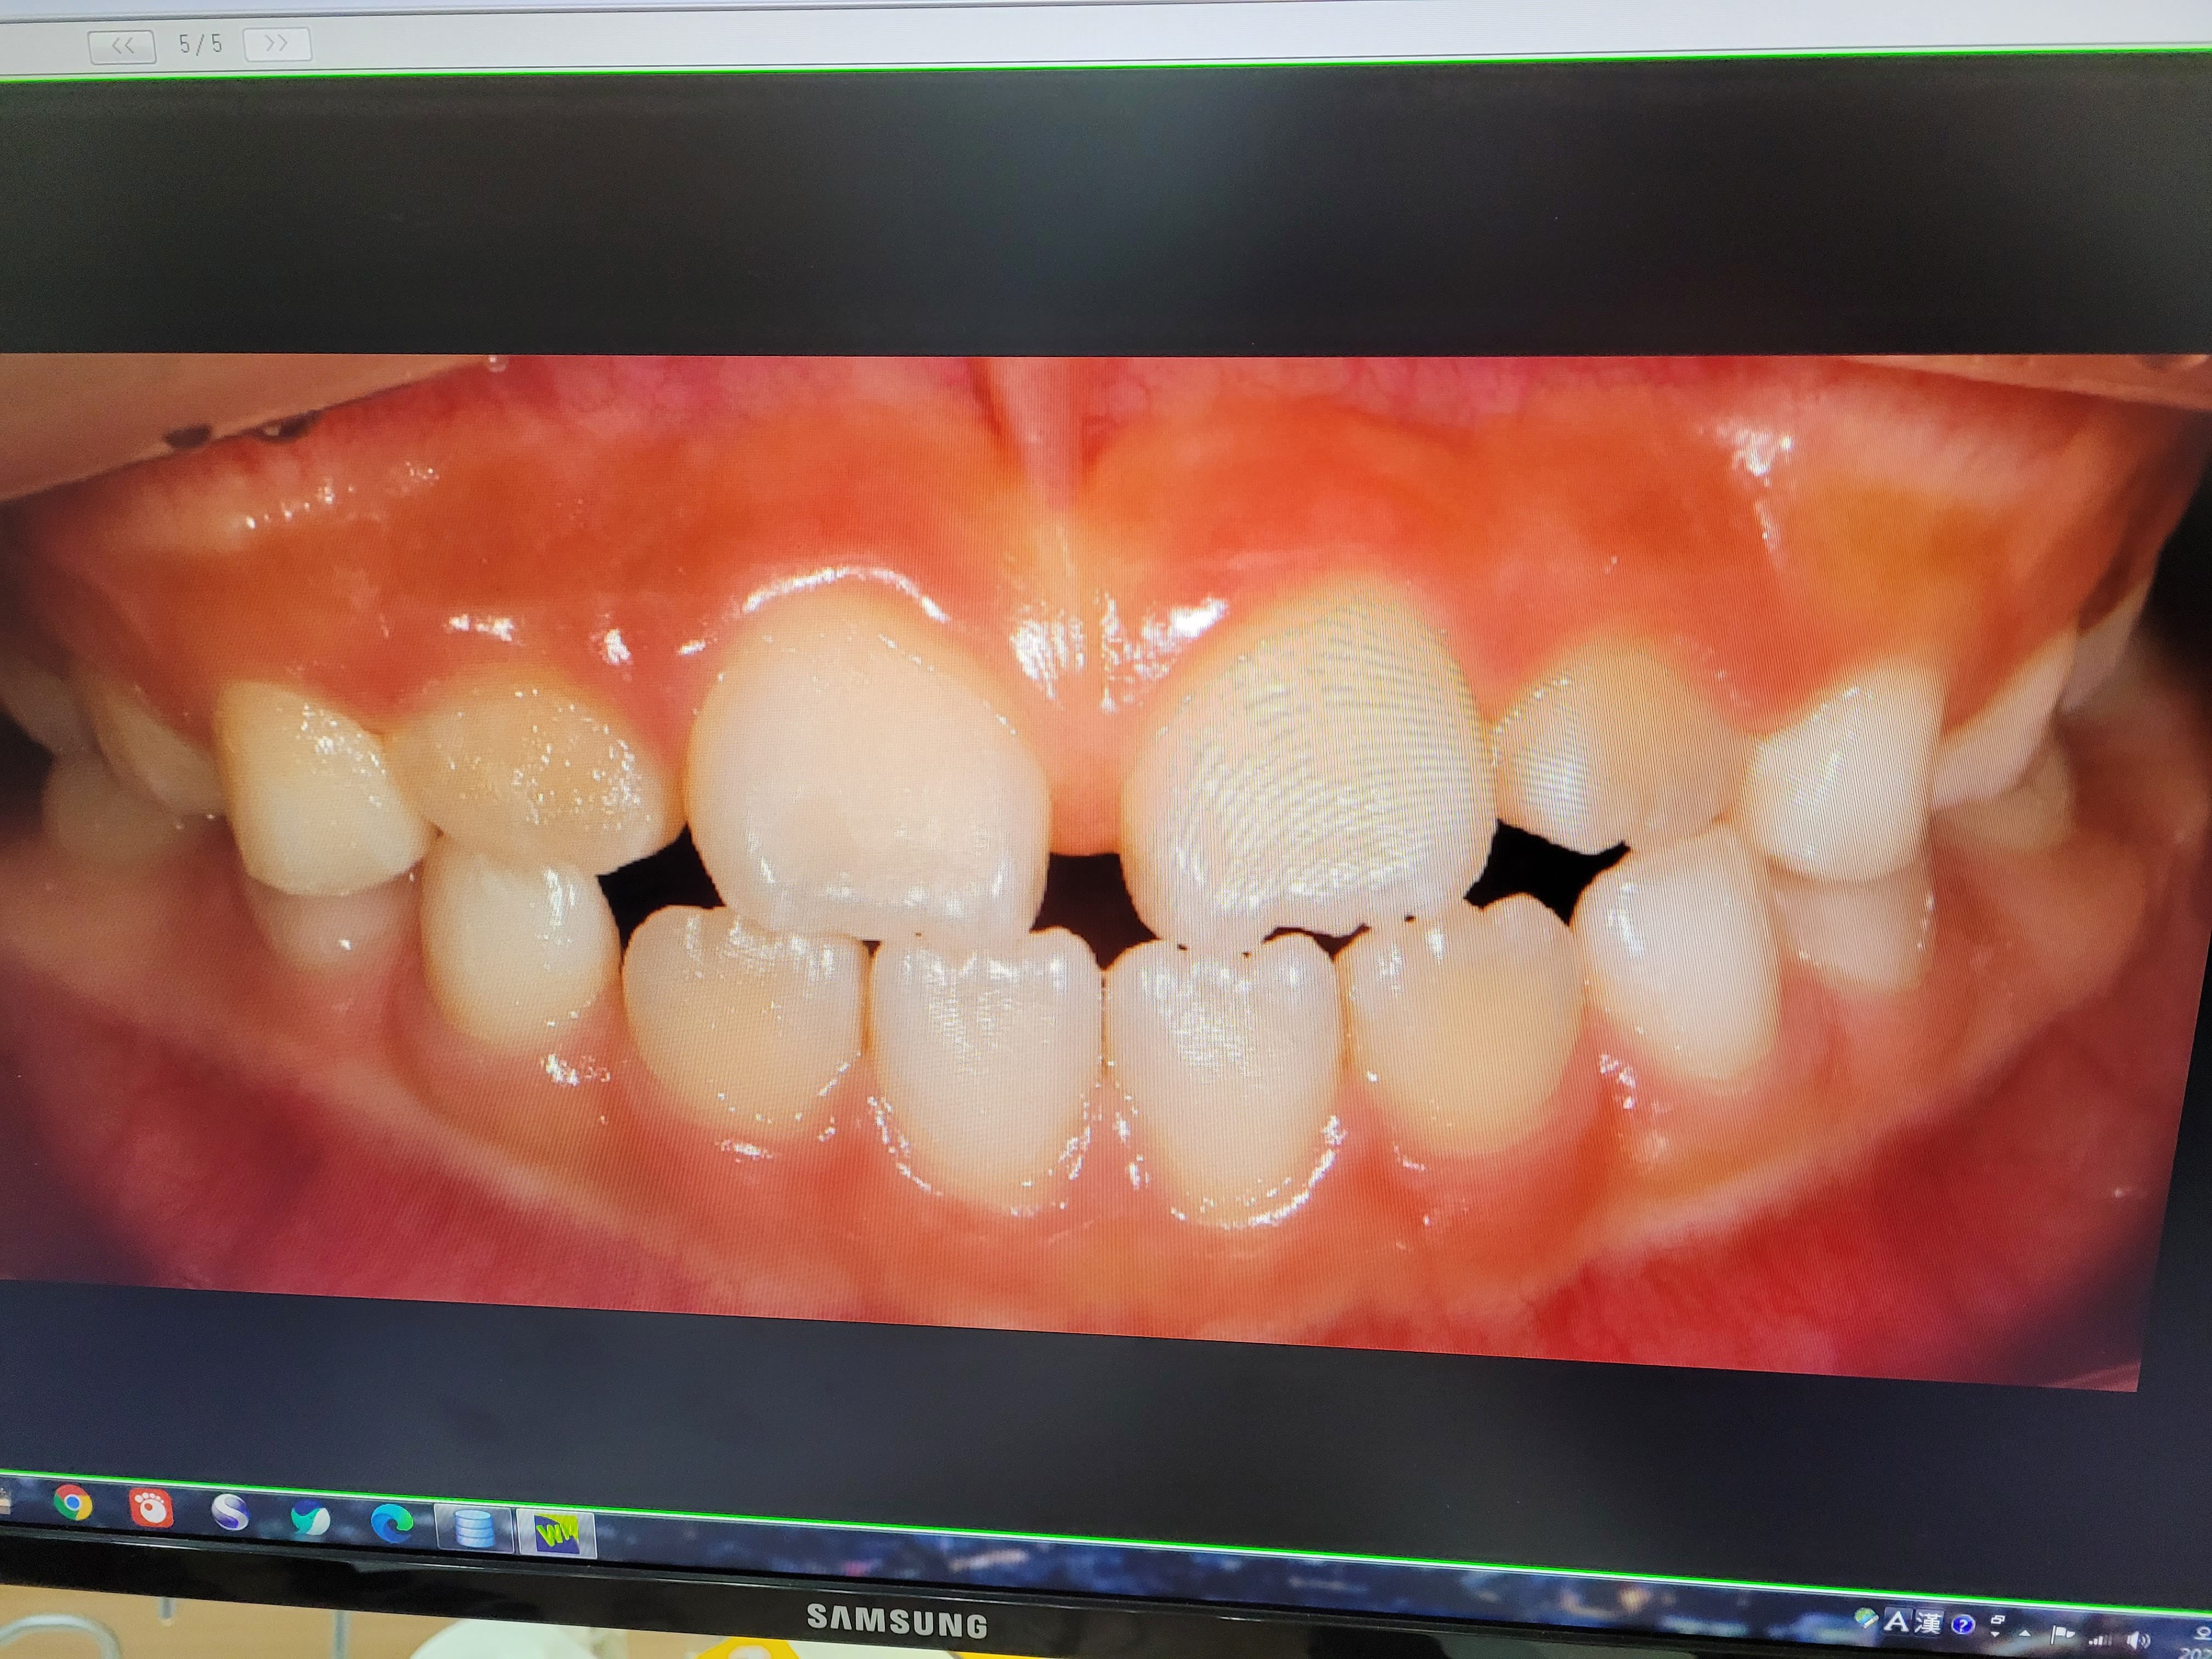

우리 딸아이가 첫 검사때 찍은 사진입니다.

지금 진행하고 있는 1차 교정은 아주 잘 되고 있다고 원장님이 말씀하셨습니다.

2차교정 여부는 아직 확인할 수가 없다고 하네요.

앞니가 벌어져 있어서 2차 교정이 필요할 수도 있지만, 송곳니가 나오면서 벌어진 앞니가 좁혀질 수 있으면 교정이 필요가 없습니다.

송곳니는 12살 정도에 나오니 그때 가봐서 필요하면 2차교정을 진행하면 된다고 합니다.